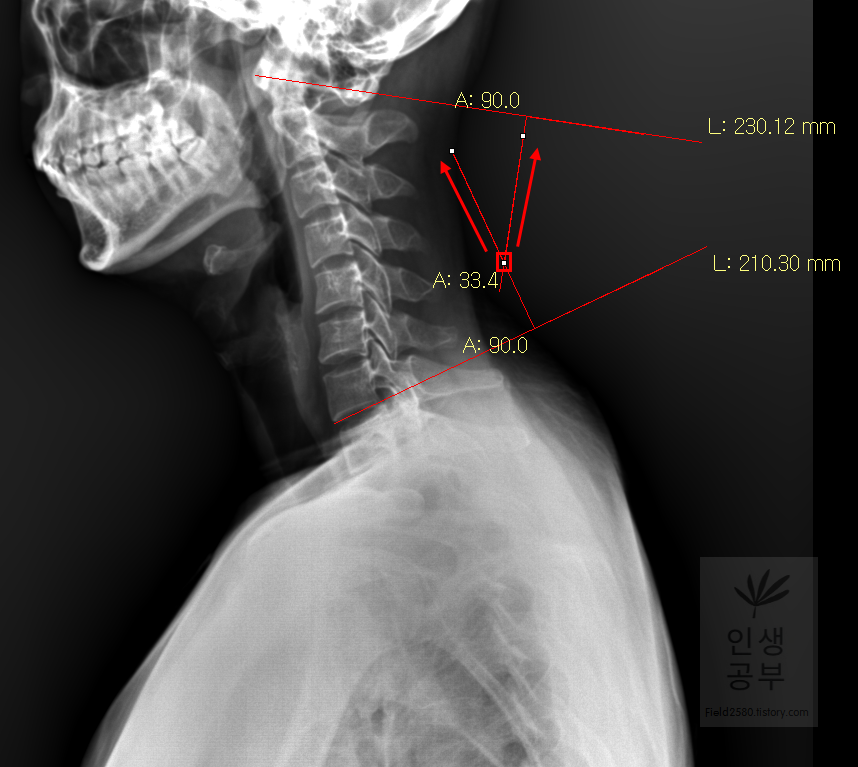

두 선이 교차된 곳에서 각도가 생기게 됩니다. 이 각도를 Cobb 각이라고 합니다. 위쪽에 각도를 재거나 아래쪽에 각도를 재어도 똑같으니 원하는 방향의 각도를 측정해 주시면 됩니다. 각도를 측정할 때에는 두선이 교차한 곳에 먼저 클릭해주고 위 화살표 방향대로 오른쪽 왼쪽의 교차한 선을 따라서 측정해 주시면 됩니다. 왼쪽선을 먼저 그어도 되고 오른쪽 선을 먼저 그어도 상관없습니다.

위와 같은 수고를 덜기 위해서 Display Workstation 프로그램에서는 간편하게 Cobb 각을 측정 할 수 있는 도구가 있습니다. 위에서 설명해 드린바와 같이 Cobb 각이 따로 있는데 각도 측정하는 버튼은 두 선이 연결된 반면 Cobb 각 버튼은 두 선이 떨어진 모양으로 되어있습니다. 빨간 네모 안에 있는 것이 Cobb 각 버튼입니다.

X-ray 아무 곳에서 찍어서 옆으로 드래그해주고 떼면 위와 같은 모양의 두 선이 나옵니다.

위쪽에 있는 선은 첫 번째 목뼈(C1) 선을 그리기 위해 제일 튀어나온 앞쪽 부분 가운데 지점에(Center of Anterior arch)에서 시작해서 후궁(Posterior arch) 제일 좁은 부위 가운데를 지나는 선이 되도록 이동해줍니다. 선 이름을 고리 뼈 선(APL : Atlas Plane Line)이라고 합니다. 점은 조금 더 정확하기 위해서 하는 것이 찍어도 되고, 점을 찍지 않은 상태에서 선을 그으셔도 무방합니다. 아래쪽에 있는 선은 일곱번째 목뼈 추체 밑면(Inferior endplate of C7)과 평행하게 선을 맞춰줍니다. 노란색 글자와 숫자가 아래줄 맞춰 준 곳에 있는데 A는 Angle 각도이고 옆에 있는 숫자가 Cobb 각입니다.